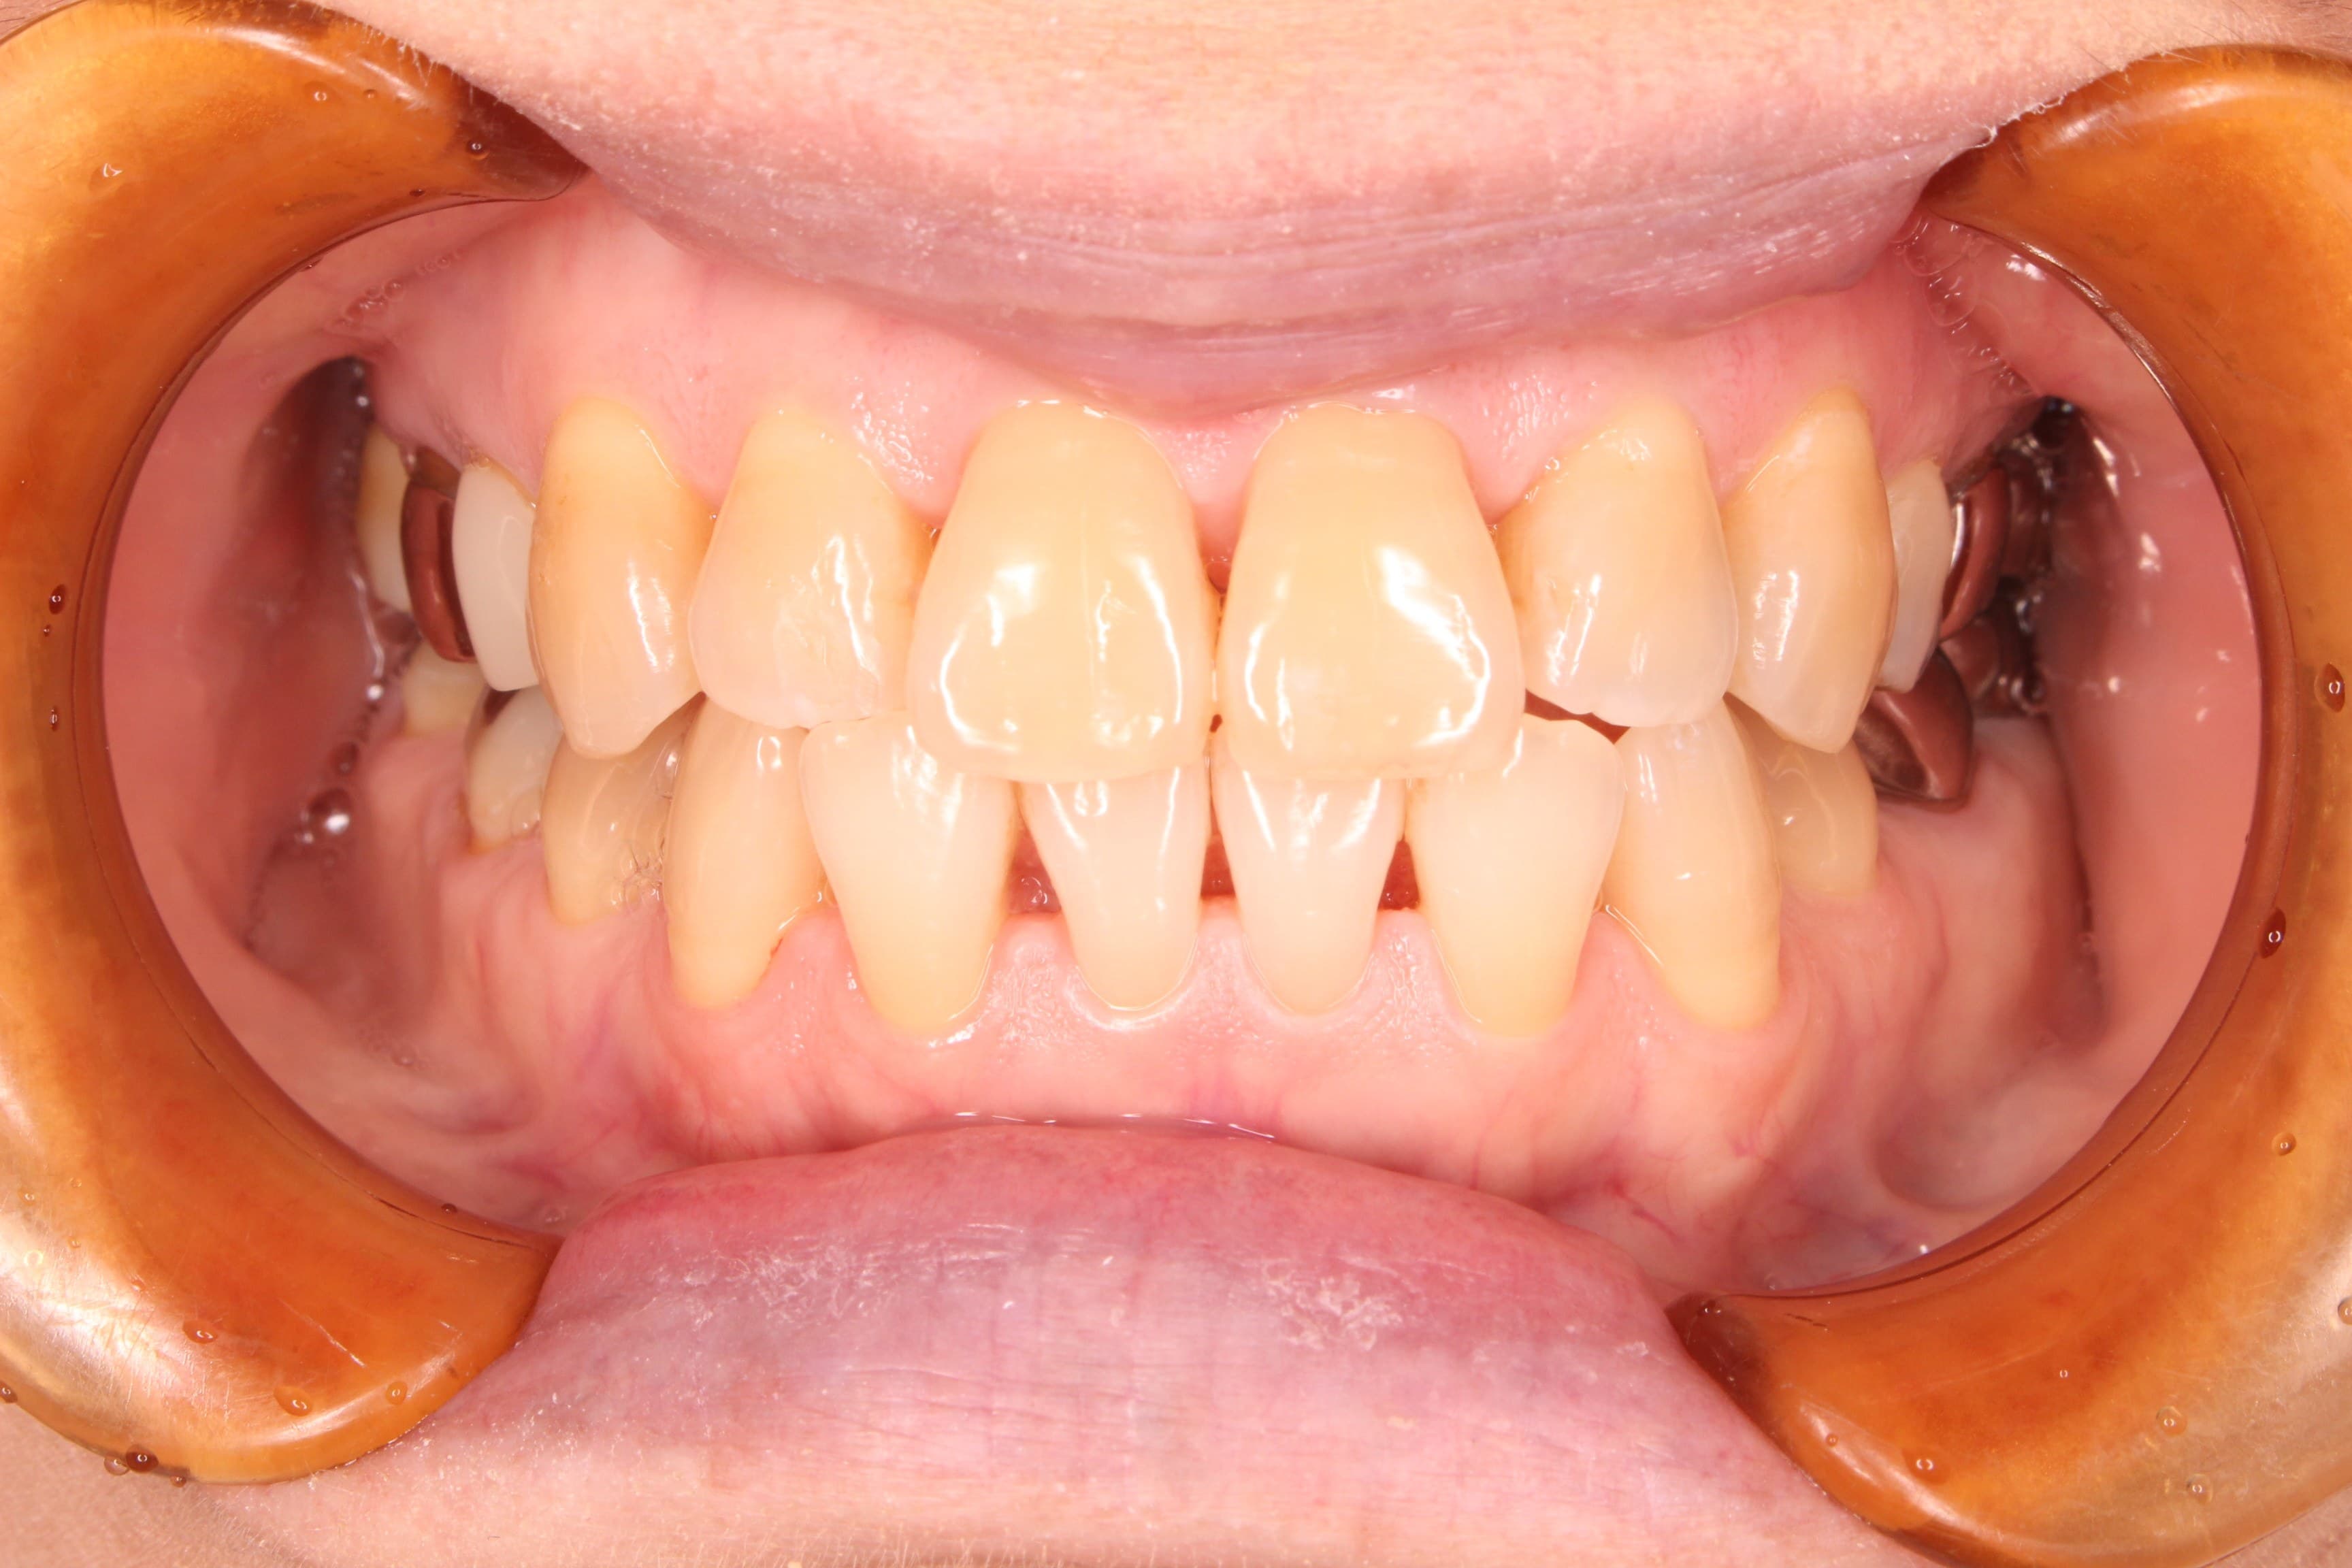

約半年間という長い期間頑張っていただいたおかげで、ブラッシングテクニックは見違えるほど上達し、磨き残しにご自身で気づいて改善していただけるまでになりました。

ネバネバや不快感も、治療終了時には改善されたそうで、私たちもとても嬉しく思います。

治療後